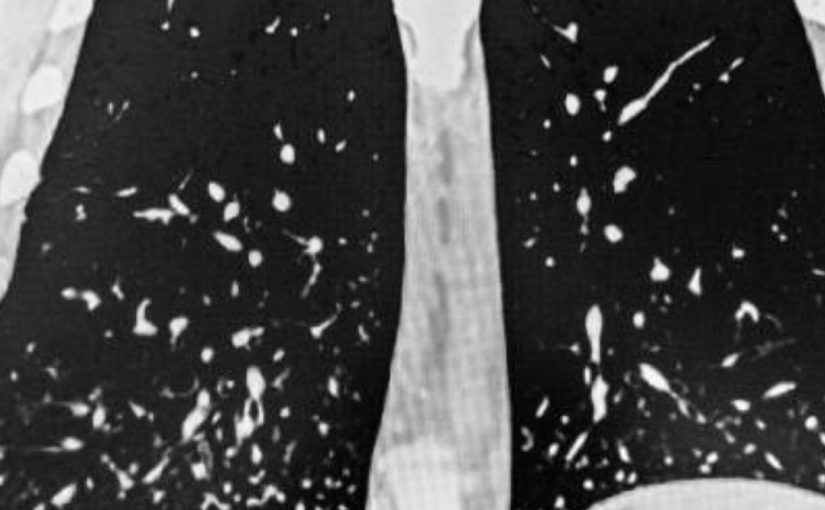

- Histoplasmose Cavitária Crônica: Nesta forma, cavidades se formam nos pulmões ao longo do tempo. Embora a infecção não se dissemine para outras partes do corpo, pode causar danos significativos aos pulmões. O tratamento com medicamentos antifúngicos, como o itraconazol, é eficaz em eliminar o fungo, mas as lesões pulmonares podem persistir, resultando em problemas respiratórios de longo prazo.